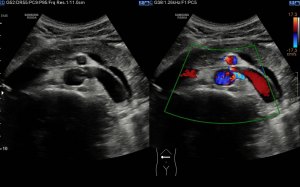

Si colocas la sonda en el mentón, en axial vas a encontrar este músculo Digástrico, que se verá muy bien, superficial, en un plano intermedio tendrás el músculo Milohiodeo y en la profundidad los músculos Geniohideos, Geniogloso y el Hiogloso…Mira:

El Músculo Milohioideo se encuentra en un plano medio, es fino y separa el plano superficial muscular, del profundo, en la imagen superior ves una pequeña porción de este músculo. En el plano profundo un grupo de varios músculos, que he mencionado más arriba y que son músculos extrínsecos de la lengua, situados en la región más medial de esta localización submentoniana estudiada.

Los vientres anteriores de los músculos Digástricos, que son el objeto del desarrollo de este Post, son dos estructuras musculares redondeadas en el corte transversal, imagen 1, y alargados si los estudiamos en el eje largo, imagen 3, mira:

Ecográficamente los músculos digástricos en eje corto tienen semiología hipoecogénica, en aspecto de noche estrellada, como la de hoy, y en el eje largo en forma de penacho o en forma de plumas con las fibras alargadas y paralelas a la superficie.